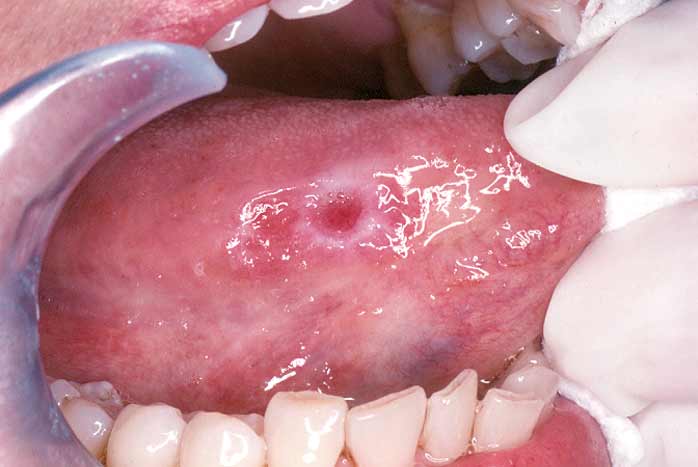

A thorough screening for oral cancer is part of your routine dental examination — another reason why you should come in to our office regularly. During the test, we will visually examine your lips, tongue, and the inside of your mouth, and check for red or white patches or unusual sores. We will feel for lumps and swellings, and gently pull the tongue aside to get an even better view. We may also use a special light, dye, or other procedure to help us check any suspect areas. If we find anything out of the ordinary, a biopsy can be easily performed.

If you notice abnormal sores or color changes in the tissue of your mouth, lips and tongue, they may be a symptom of oral cancer — most, however, are completely benign. But sores or other unusual changes that haven't gone away by themselves after 2-3 weeks should be examined in our office. Remember, the only way to accurately diagnose oral cancer is through a laboratory report. Early diagnosis, aided by thorough screenings at your regular dental checkups, is one of the best defenses against oral cancer.